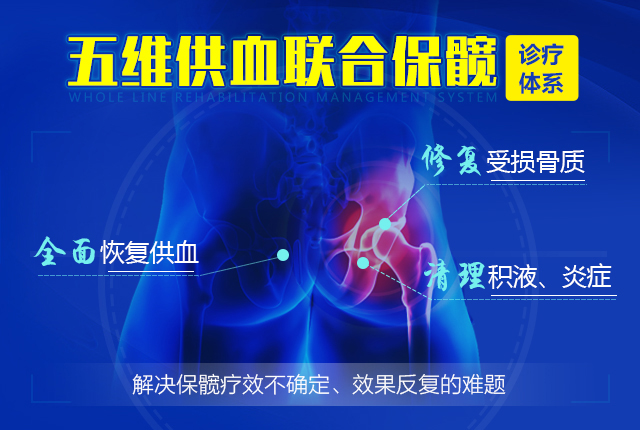

全面恢复供血原因

通过五维层级递进供血,全面恢复股骨头周围供血,打通供血,药物、营养通道,疼痛症状消失、关节受限解除;达到从根源上终止疾病发展,阻断病情反复的目的。

修复坏死骨质原因

清理、修复受损骨质,促进新骨再生

通过彻底清除关节腔内积液、炎症及游离物质,促进坏死骨质再生,改善跛行、受限症状,避免置换。